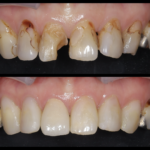

痛くない虫歯・・?

こんにちは!院長の渡辺です。 本格的な寒波がきていますが体調崩されたりしてないでしょうか? 風邪をひくと咳や熱がでますね、転んで擦りむくと痛みや血がでます。 虫歯はどうでしょう?冷たいものがしみたり、ずきずきしたりといった症状があればわかりやすいですが。。 実は無症状に進む虫歯もあります。 特に大人は歯の中にある神経が子供に比べると細いので痛みがですそのままじわじわと進行していくことも珍しくありま...